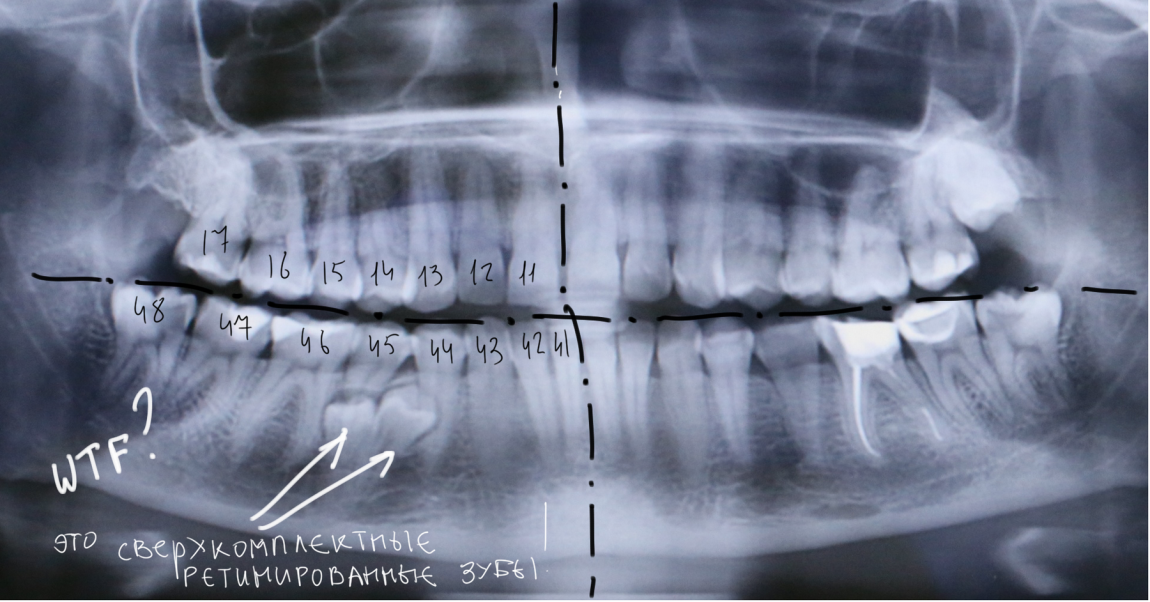

У некоторых людей развивается не 32, как обычно, а 33 или 34 зуба. А иногда и больше. Такие "лишние" зубы называют сверхкомплектными и, если говорить честно, ничего кроме проблем они в себе не несут.

Стоматологи много пишут о зубах мудрости, и этим уже никого не удивишь. Для нас это обычное дело, часть ежедневной практики. Для обычных людей удаление зубов мудрости, не говоря уже об удалении сверхкомплектных зубов - это всегда исключительное переживание. И когда нестоматолог рассказывает о своём опыте и делает из него ... Читать дальше

Примерно полтора года назад к нам в клинику обратилась молодая и красивая девушка. Все бы ничего, ничто ее не беспокоило, но вот однажды пошла она лечить зубки, и ей сделали панорамный снимок. Сделали панорамный снимок - забегали, заохали, послали на компьютерную томографию.